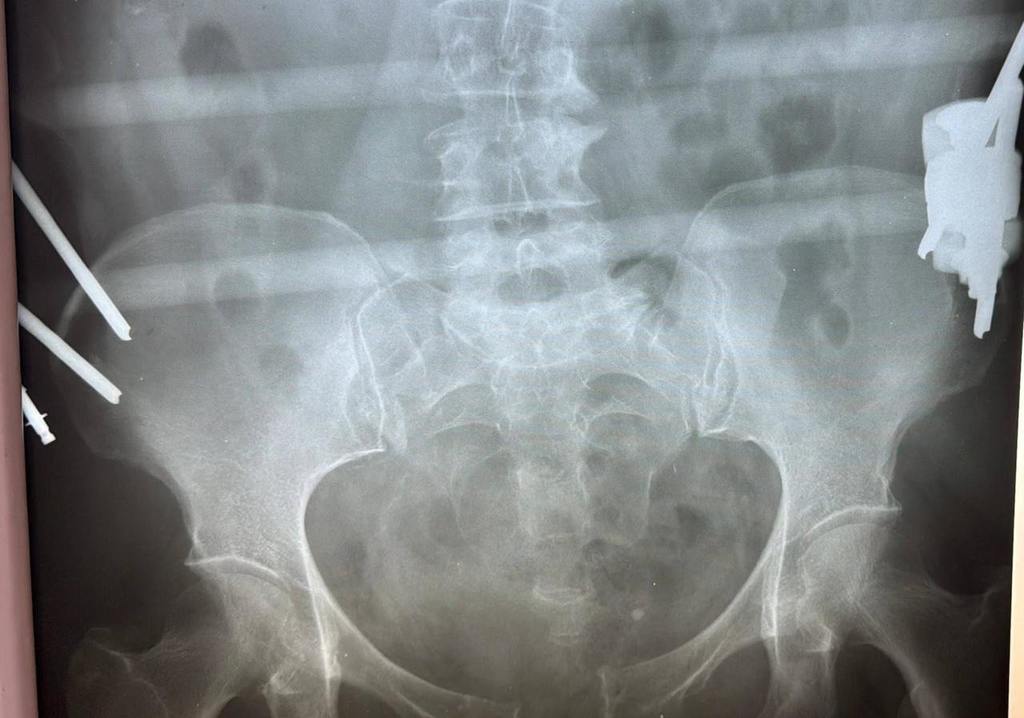

В ходе обследования врачи диагностировали сочетанную травму — разрыв лонного и крестцово-подвздошного сочленений, которые соединяют различные кости таза и играют важную роль в поддержании вертикального положения тела и распределении нагрузки. Было принято решение провести хирургическое лечение.

— Мы выполнили остеосинтез, то есть соединили обломки костей. Чтобы правильно их закрепить использовали специальные пластины и винты. В последующем их не потребуется удалять. И пластина, и винты из титана — биосовместимого материала, который не вызывает негативных реакций со стороны организма, и никак не помешает пациентке, — рассказал травматолог-ортопед Чеховской больницы Салман Асламханов.